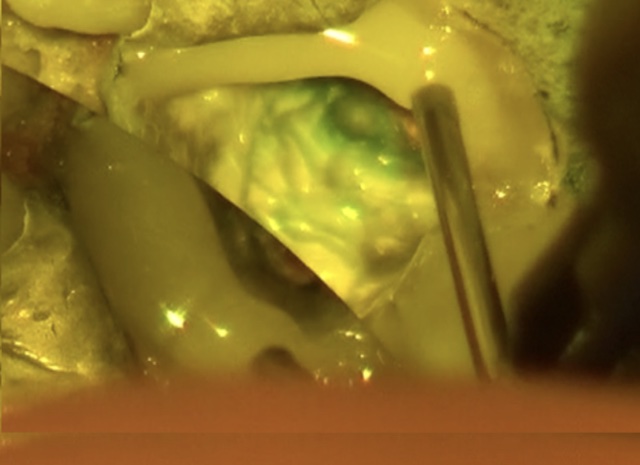

虫歯を除去後、神経が露出しないように丁寧に削合しました。